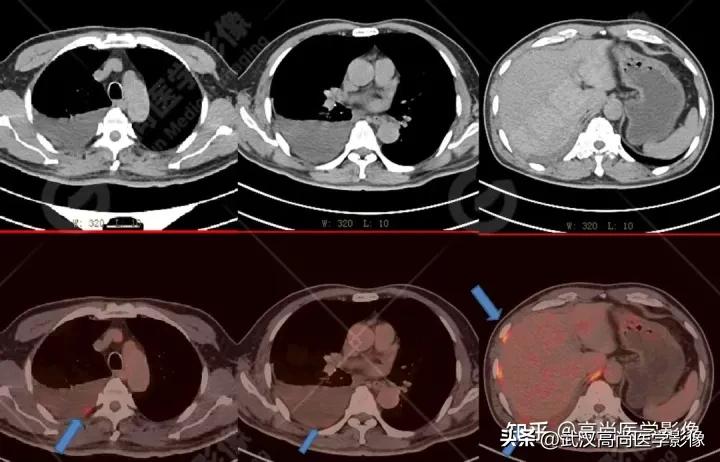

影像表现:

右肺下叶背段见一实性结节,大小约2.0cm×1.6cm×1.8cm,CT值33Hu,FDG高摄取,SUVmax13.0。

恶性CT征象:

病灶边缘分叶、短毛刺,其近端亚段支气管截断,瘤肺界面清楚,病灶远端片絮状阻塞性炎症。

PET/CT诊断结论

右肺下叶背段周围型肺癌,伴多发淋巴结、左侧小脑半球、肝脏、骨多发转移。